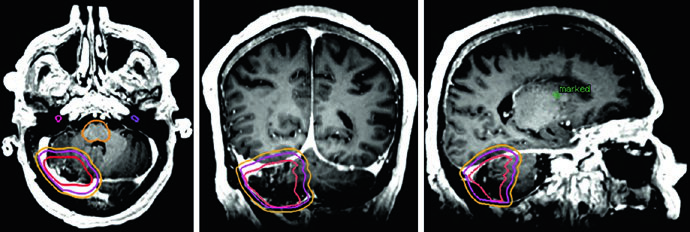

Meningioma Atípico e Maligno: Graus II e III da OMS

Os meningiomas são os tumores intracranianos primários mais comuns em adultos. Menos de 30% são classificados como atípicos (OMS grau II) ou malignos (OMS grau III). O manejo radioterápico desses subtipos difere substancialmente do meningioma benigno.

Para meningioma grau II, a radioterapia adjuvante pode ser considerada após ressecção macroscópica total e é recomendada após ressecção subtotal. Para grau III, a radioterapia é recomendada para todos os pacientes independentemente da extensão da ressecção. Para conhecer o manejo dos tumores benignos do SNC, confira nosso artigo dedicado sobre tumores benignos do SNC.

Um detalhe crítico que diferencia os meningiomas de grau II e III: como esses tumores podem invadir osso e parênquima cerebral, crânio e encéfalo normal não funcionam necessariamente como barreiras naturais à disseminação. Se os achados operatórios ou anatomopatológicos indicam invasão cerebral, as margens devem incluir o parênquima em risco. E para tumores recorrentes de grau II, é essencial avaliar a inserção dural original no diagnóstico inicial — ela pode ter sido sede de doença microscópica.

Volumes-alvo para meningioma grau II/III e hemangiopericitoma

| Meningioma grau II (upfront) | 54–59,4 Gy (1,8 Gy/fx) | Cavidade pós-operatória, tumor residual incluindo envolvimento dural/ósseo suspeito na T1 pós-contraste | 0,5 cm restrito anatomicamente | 0,3–0,5 cm |

| Meningioma grau II (recorrente) | 54–59,4 Gy (1,8 Gy/fx) | Idem + avaliação da inserção dural prévia no diagnóstico inicial | 0,5–1,0 cm restrito | 0,3–0,5 cm |

| Meningioma grau III (upfront ou recorrente) | 59,4–60 Gy (1,8–2 Gy/fx) | Idem + inserção dural prévia | 1,0–1,5 cm restrito | 0,3–0,5 cm |

O hemangiopericitoma merece menção especial. A expansão de CTV de 1,5 cm segue o padrão, mas diferentemente dos meningiomas, todo o osso envolvido deve ser incluído no volume sem redução em barreiras ósseas — a natureza infiltrativa desse tumor justifica essa conduta mais agressiva.